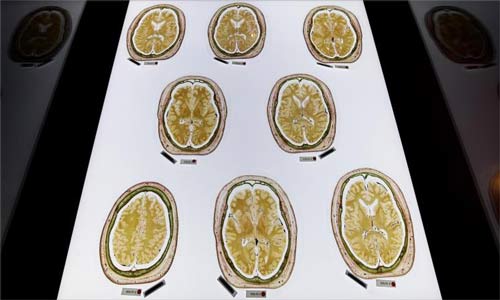

◄رصد باحثون نشاطاً كبيراً في المخ عند إثارة فضول الإنسان حول موضوع معين، ويشمل النشاط أماكن معينة في المخ تساعد على تقوية الذاكرة.

ورصد الباحثون نشاطاً أثناء فترات الفضول في مناطق المكافأة في المخ، وهي التي تحسن بشكل كبير من قوة التذكر.